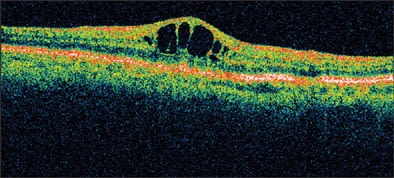

Clinically significant CME, by definition, is associated with a reduction in visual acuity. These patients usually have angiographic CME and obvious macular changes. Spaide and others have noted that clinically significant CME is most likely to occur in patients having complicated surgery and vitreous loss or implantation of an anterior-chamber intraocular lens (IOL).5 With the advent of new diagnostic instrumentation, even subtle changes in retinal thickness can now be detected (Figure 2). With the availability of advanced technology, including optical coherence tomography (OCT) and premium intraocular lenses, the expectations of both patients and clinicians have become significantly increased. McColgin and his colleagues reported that CME, defined as increased retinal thickness, occurred in 12% of patients following uncomplicated cataract surgery.20 It should be noted that while most patients with pseudophakic CME do not have quantitative reduction in their visual acuity, many patients do complain of persistent reduced contrast sensitivity and color desaturation, despite treatment and normal recorded Snellen vision.

IMAGE APPEARS COURTESY OF KING Y. LEE, MD.

Figure 2. CME as indicated on Heidelberg OCT.

Recent advances in cataract surgery have led to excellent outcomes, rapid recovery, and increased patient expectations. The utilization of premium multifocal IOLs that reduce contrast sensitivity and increase patient expectations make the presence of any retinal thickness potentially significant. Perhaps this will be the stimulus for us to redefine what really represents clinically significant macular edema.